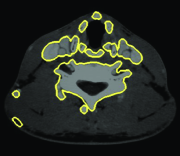

Similar interaction is utilized in 3D live-wire (Hamarneh et al., 2005) as implemented in the TurtleSeg software222www.turtleseg.org (Top and et al., 2011; Top et al., 2011). In 3D live-wire, few slices in different orientations of a 3D volume are segmented using 2D live-wire. Then, the segmented 2D slices are used to segment the whole 3D volume by generating additional contours on new slices automatically. The new contours are obtained by calculating optimal paths connecting the points of intersection between the new slice planes and the original contours provided semi-automatically by the user.